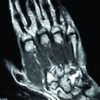

After initial examination, the patient reported with X-ray and magnetic resonance imaging (MRI). A plain X-ray (Fig. 1) of the wrist showed a destructive lytic lesion over the distal radius which had ill-defined margins, lytic lesions also seen in the base of the 2nd and 3rd metacarpal base. MRI report (Fig. 2 and 3) showed an osteolytic lesion measuring 2.5 × 2.4 cm distal end of radius extending to a subarticular location with extraosseous soft-tissue component breaching the volar surface of distal radius. Multiple lytic lesions involving the trapezium, trapezoid bone, and capitate bones with associated marrow edema lytic lesions are also seen in the base of 2nd and 3rd metacarpals with enhancing soft tissue lesion measuring 2.9 × 2.1 cm abutting the carpal bones also seen. This was followed by whole-body positron emission tomography-computed tomography (CT) scan (Fig. 4) which revealed increased fluorodeoxyglucose uptake of standardized uptake value Max-5 in the distal radius with soft-tissue component and involvement of multiple carpal bones as described in MRI reports.